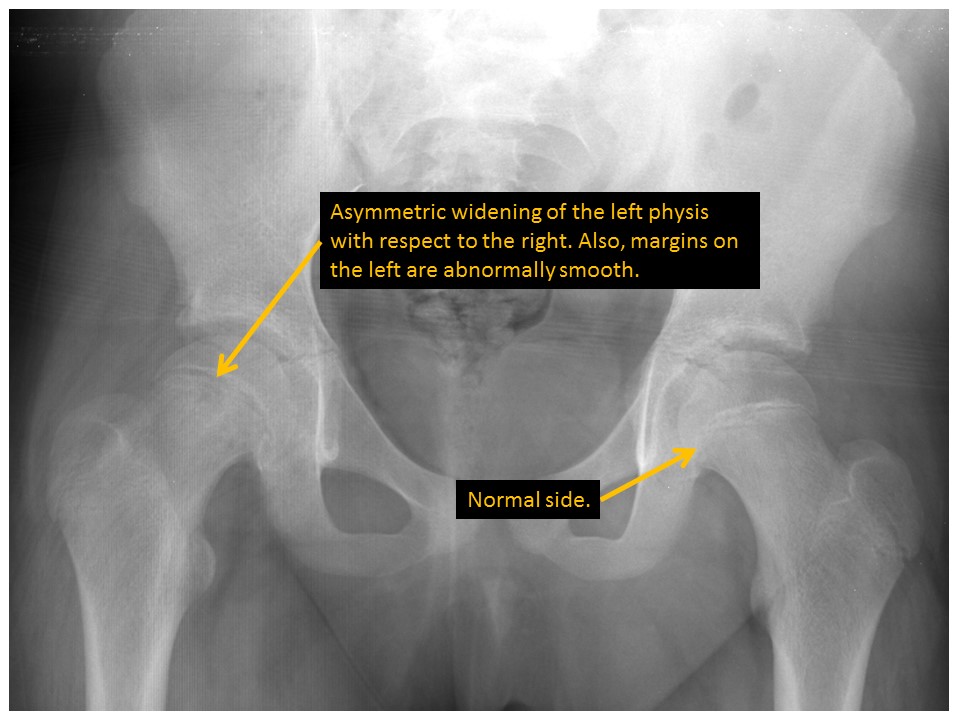

The proximal femoral physes are widened or abnormally smooth or irregular in contour. [Yes/No]

Klein lines asymmetrically cross the femoral epiphyses or there is displacement of the femoral epiphyses with respect to the femoral necks. [Yes/No]